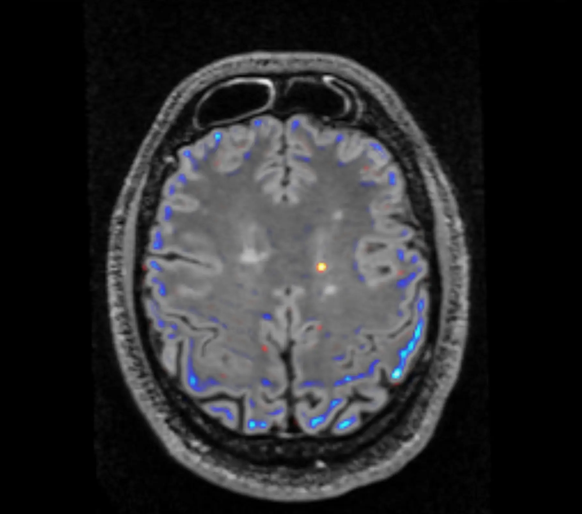

Besonders in der radiologischen Diagnostik hat sich die Technologie etabliert. Denn die Analyse von Bildern und das Erkennen von Krankheitsmustern lassen sich mit Machine Learning sehr gut trainieren. Algorithmen finden Brustkrebs-Knötchen im schwarz-weissen Ultraschall eher als menschliche Augen. Es gibt bereits eine Fülle von Programmen, die im Krebs-Screening mehr Tumore erkennen als erfahrene Ärzte.

Am meisten von der Technologie profitiert haben dürften bisher schwere Raucher, weil die meisten KI-Anwendungen Lungentumore erkennen. Aber auch Leute mit Gefässverengungen, beispielsweise Herzinfarktgefährdete oder Menschen mit Hirnschlagrisiko, werden dank der KI besser diagnostiziert. Justus Roos, Radiologiechefarzt am Luzerner Kantonsspital, erklärt: